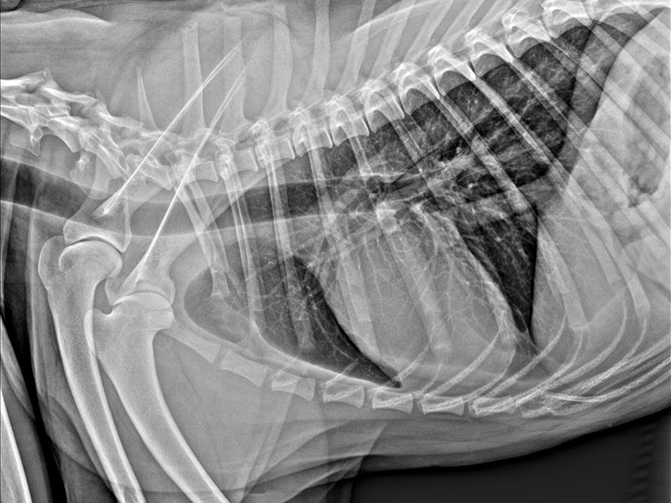

微焦点球管、微像素平板探测器以及高级图像处理算法是获取优越图像的黄金搭档,实现精准成像,提高病灶检出率。

舒博尔XVIEW-体化图像采集处理软件,具有强大的图像算法处理能力和人性化的操作流程,从登记-拍摄部位选择、采集处理图像、报告打印输出一气呵成,智能的动物解剖部位预设程序,可以根据动物类型、部位、体型自动调出高压曝光参数,使曝光参数的选取变得非常简单。图像处理算法根据不同的动物的组织密度差异进行了细分处理,确保各种动物拍摄均能获取优异的图像质量,专业的辅助诊断测量。I具包含VHS (脊柱心脏评分)等,极大的帮助医生进行病患诊断。